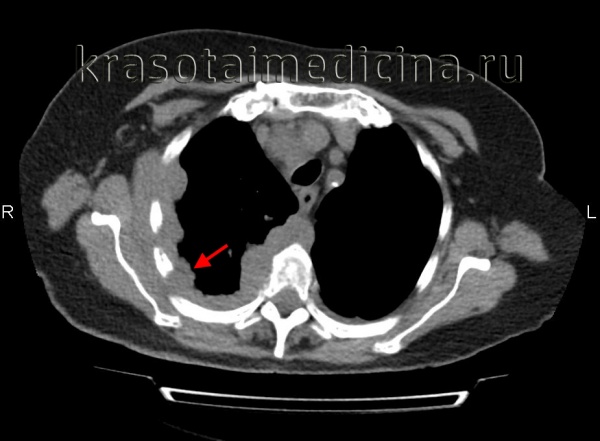

Обычно при этом опухоль распространяется на операционный шов, что причиняет больному дополнительную боль. Для оценки распространения опухоли необходимо провести КТ, особенно близлежащей области плевры и перикарда.

Окончательное подтверждение диагноза и определение стадии мезотелиомы плевры становится возможным после выполнения КТ или МРТ легких. На томограммах отчетливо визуализируется узловое утолщение плевры и междолевых щелей, плевральный выпот, прорастание опухолевых масс в грудную стенку, средостение, диафрагму и т. д.